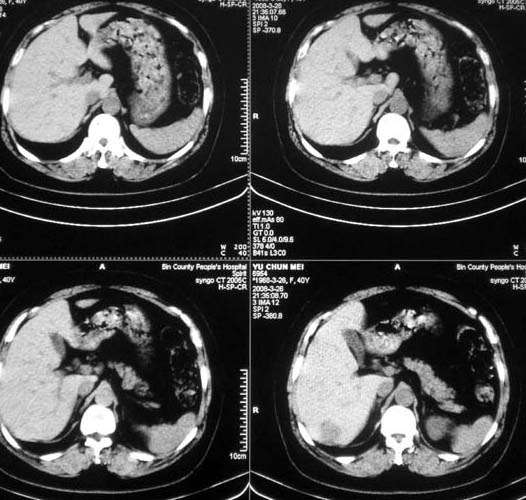

女,56岁,和上两个是同一病人,腹痛,胀痛,消化不良,五年前有血管瘤。密度减低影ct值为40hu。

肝内占位性病变:肝血管瘤可能性大,建议必须增强扫描。

肝内多发低密度影,边缘清楚,结合病史考虑:肝血管瘤可能性大,建议必须时增强扫描。